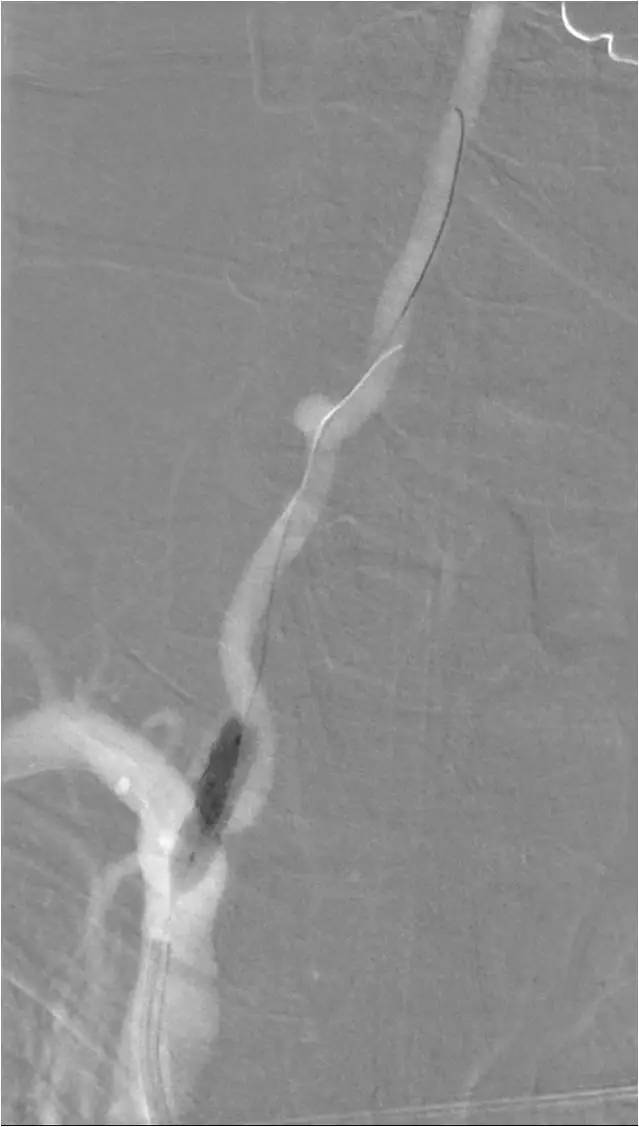

再送一Transcend微导丝(0.014″,300cm),先后越过近远端狭窄,其后微导丝顶端轻抵成角管壁成一大的“回头袢”,再将微导丝远端送至基底动脉顶端(图9)。

图9

沿微导丝送入球扩式Apollo(3.0mm×8.0mm)准确定位后扩张球囊释放支架(图10)。

图10

其后造影显示无明显残余狭窄,前向血流TICI3级(图11)。

图11

撤出支架输送系统,保留微导丝,送入Blue球扩式支架(5.0 mm×12mm),扩张释放于近端狭窄(图12)。

图12

最后造影显示支架贴壁良好,前向血流好(图13)。

图13